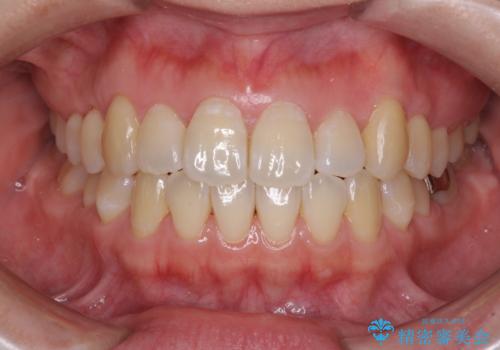

切端咬合をインビザライン矯正で解消

切端咬合はスムーズに解消され、前歯の負担を軽減させることができました。